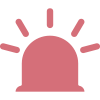

Flag Towards Precise Screening of Infectious Mononucleosis (IM)

DIFF 3D scattergram

3D Scattergram of typical infectious mononucleosis

Alert precisely for reactive lymphocytosis caused by infectious mononucleosis

through the distribution characteristics of scatter plots

Reactive Lymph-IM?